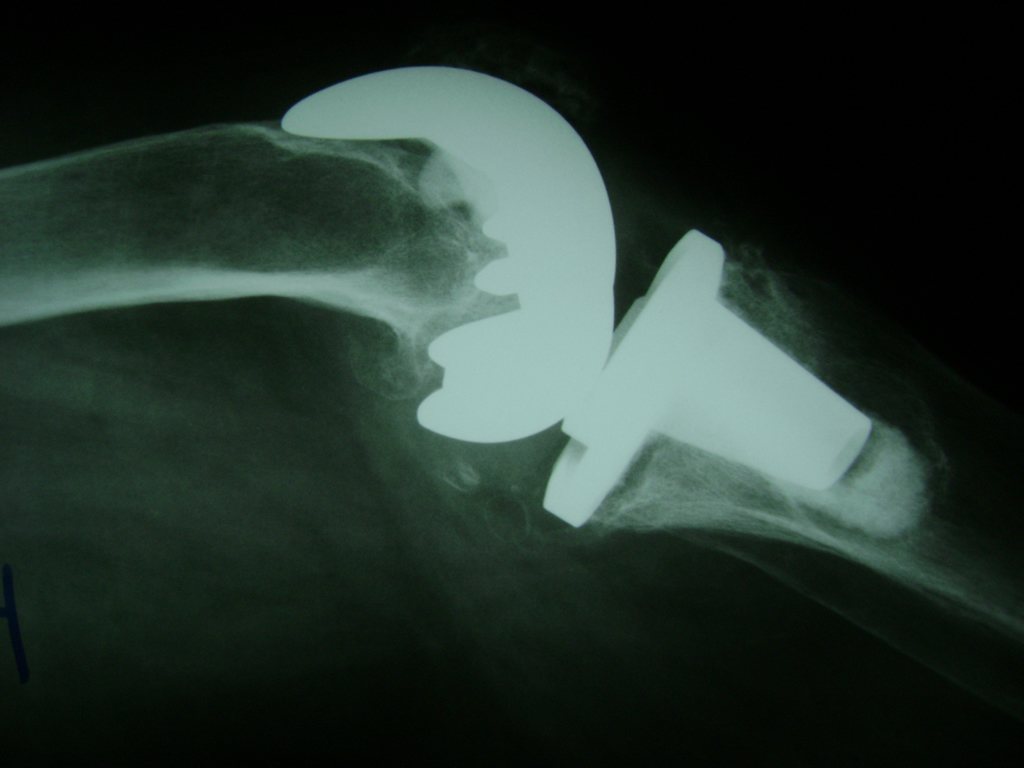

Fémur - Rodilla